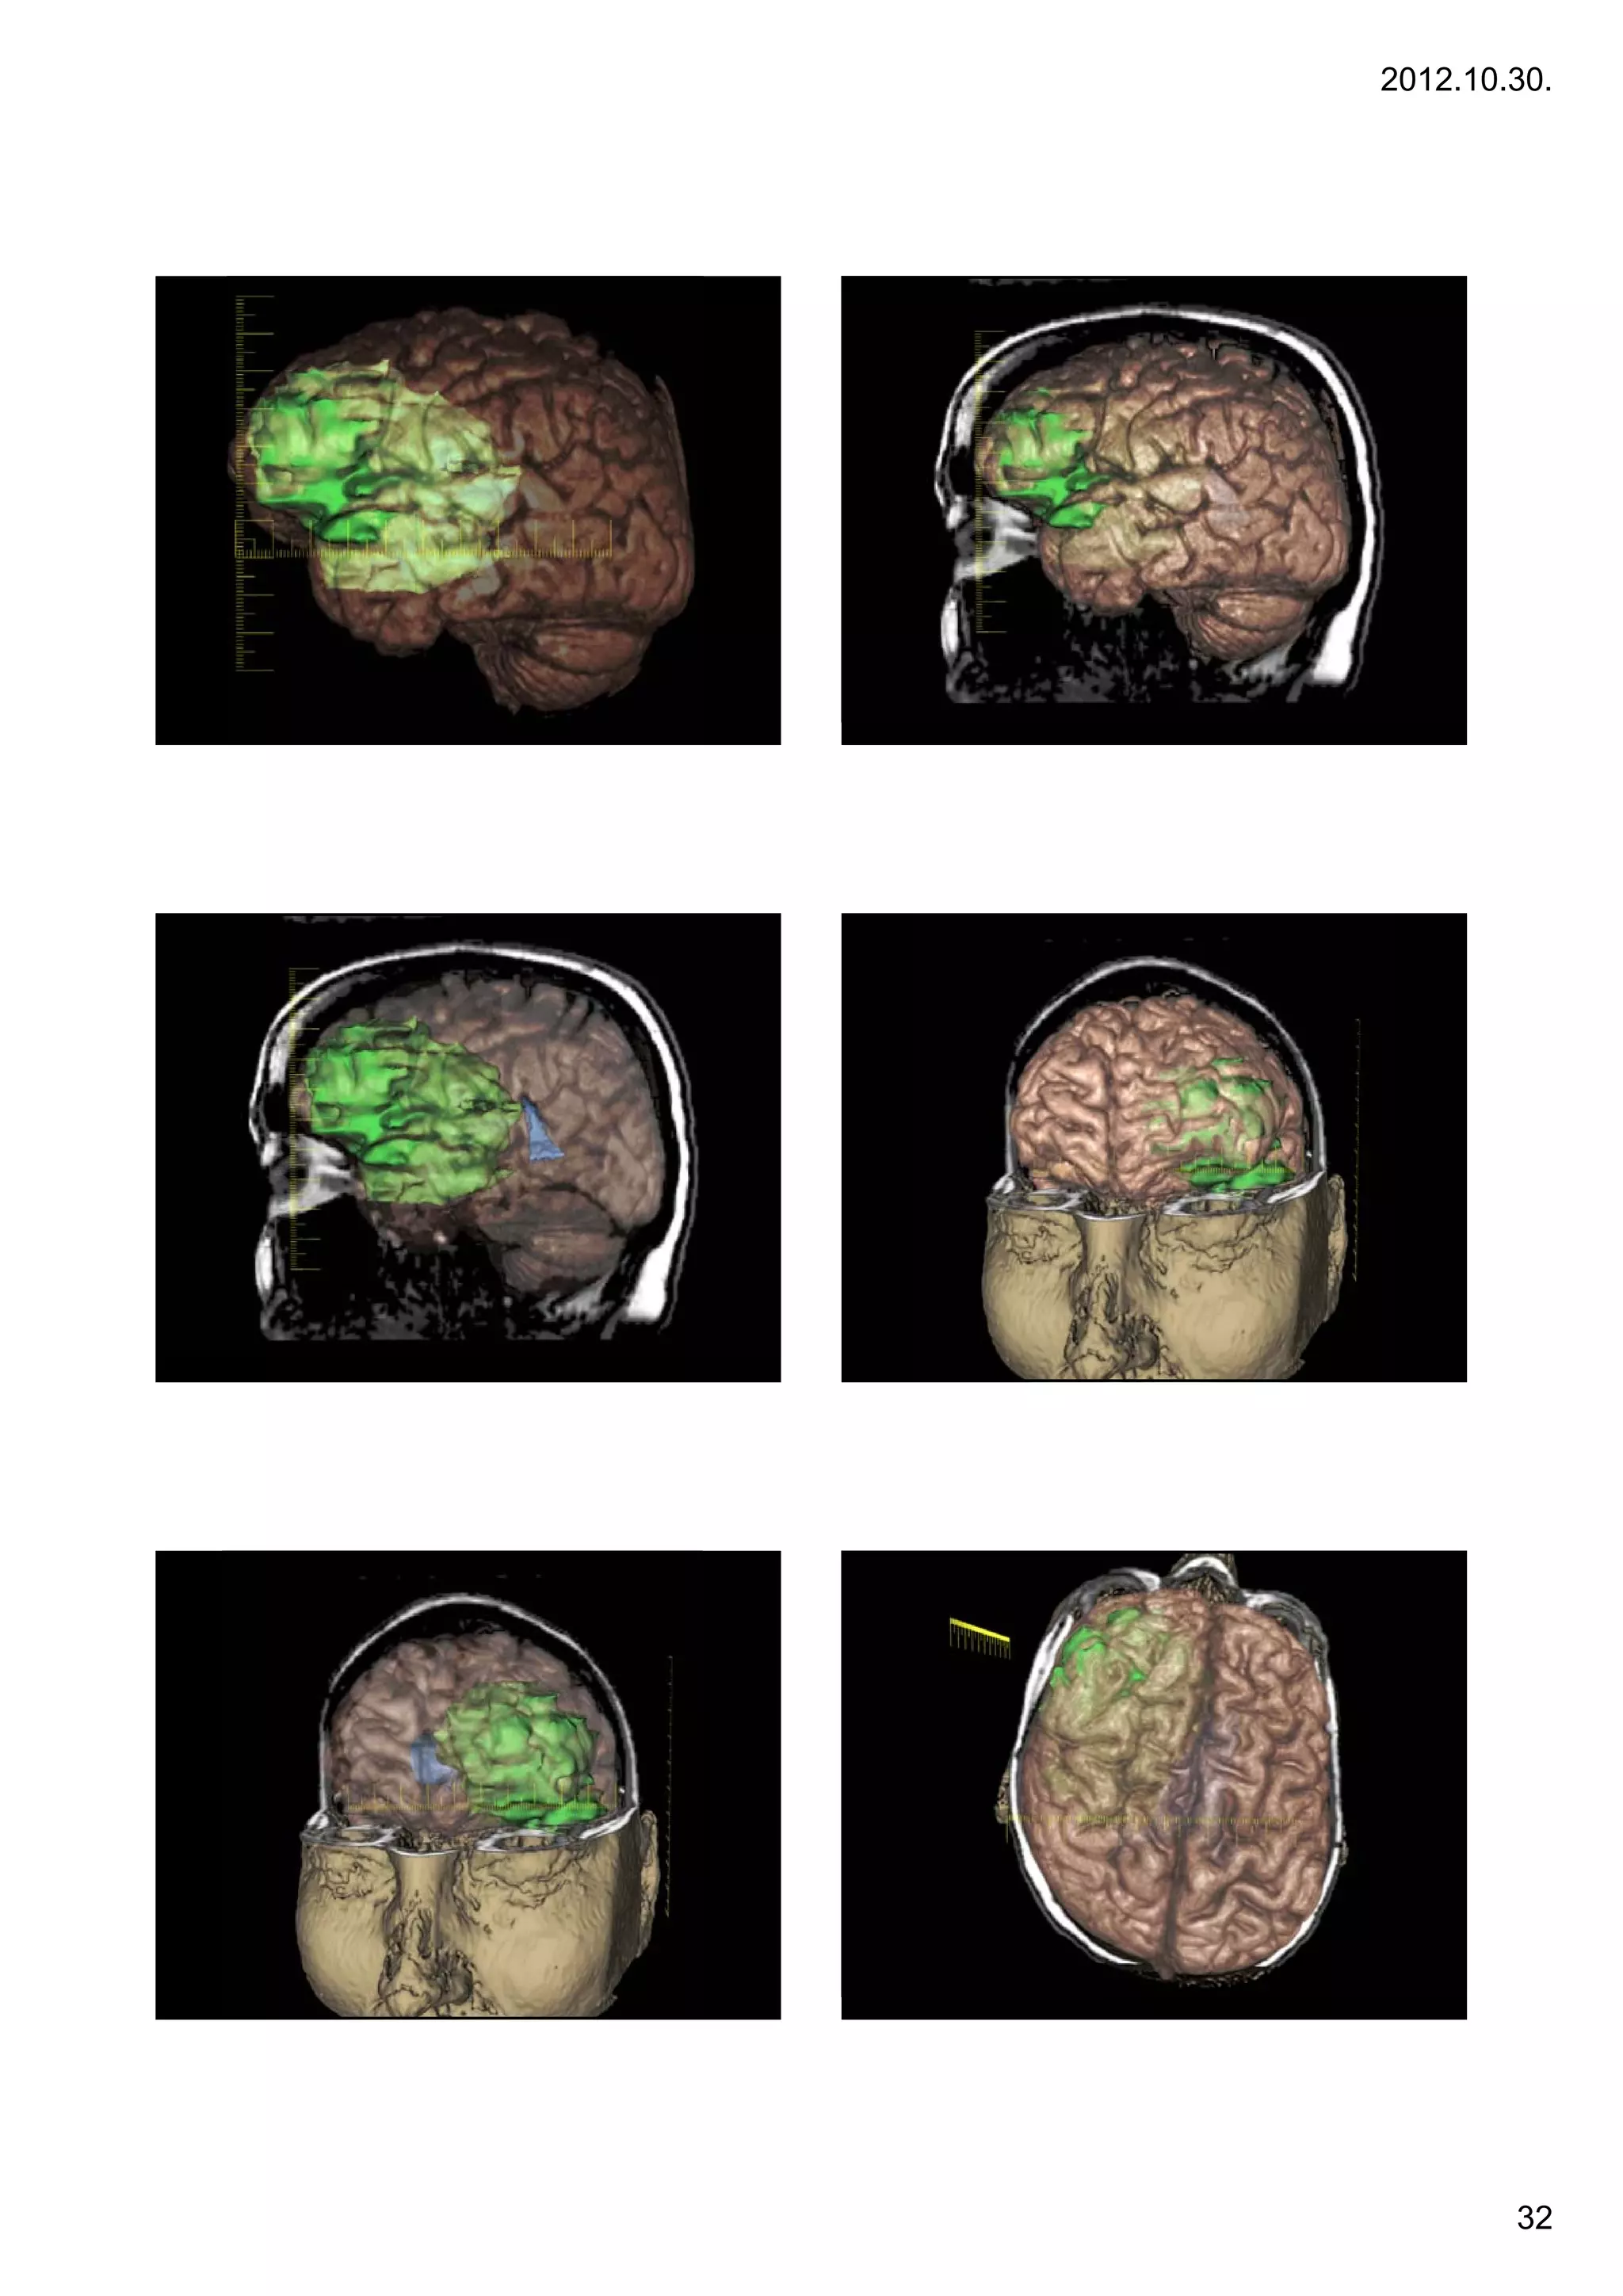

Case 7. – large GBM

Treatment: d b lki

T           debulking

32